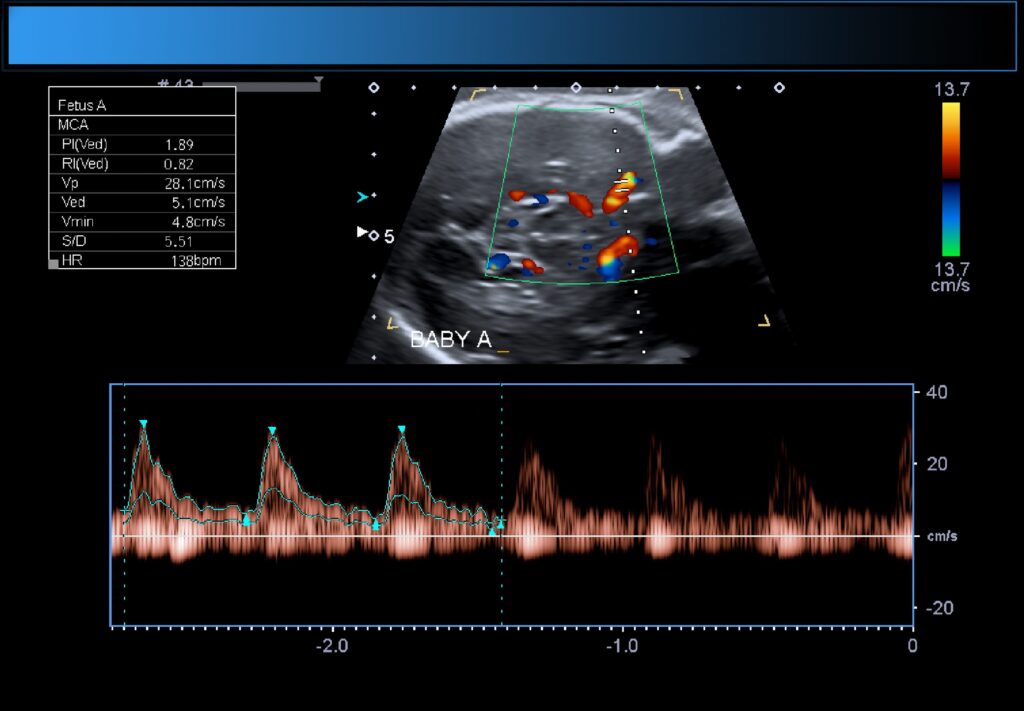

Beoordeling doppler en vruchtwater

Bij een kleine groep kindjes is het nodig ook de doorbloeding van verschillende bloedvaten te meten. We noemen dit een doppleronderzoek en ook deze metingen gebeuren met behulp van een echo. Het meten van de doppler wordt met name gedaan bij kleine kindjes. Door de doorbloeding van de verschillende vaten te meten, krijgt de gynaecoloog meer duidelijkheid over de conditie van de baby op dat moment.